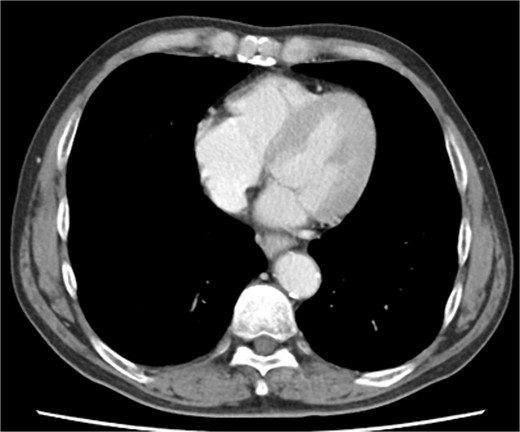

The patient underwent robotic subtotal esophagectomy, two-region lymph node dissection, narrow gastric tube was created by hand assisted laparoscopy and cervical anastomosis was performed via the retrosternal route. The operation took 613 min, with minimal blood loss. The retrosternal route under camera assist was created without bleeding, and no intraoperative hemodynamic changes or complications were observed. The pathological stage was pT1b(SM2)pN1M0 pStage II (Japanese Classification of Esophageal Cancer, 12th Edition). Esophageal fluoroscopy on postoperative day (POD) 7 showed a minor leak at the anastomotic site, which improved by POD 14 after cervical wound release and drainage. The minor leak at the anastomosis site has been the cause of prolonged hospital stay. The patient experienced sudden intermittent chest pain on POD 17, but his vital signs remained stable. Echocardiography revealed an increased amount of pericardial fluid. He was diagnosed with pericarditis and prescribed colchicine by cardiologist; however, pericardial fluid levels continued to increase. Pericardiocentesis with pericardial catheter insertion was performed on POD 34, revealing bloody pericardial fluid. Blood drainage persisted at approximately 300 ml/h. Urgent contrast-enhanced CT revealed contrast extravasation from the anterior right ventricle (Fig. 2). Coronary angiography revealed aneurysmal changes in the peripheral right ventricular branch without apparent hemorrhage (Fig. 3).

Coronary angiography reveals aneurysmal changes in the right ventricular branch without evident bleeding (arrow).